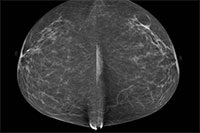

Prior research has shown an association between breast density and breast cancer. In addition, cancers in dense breast tissue are more difficult to see on mammograms. As a result, some women with dense breasts are advised to get supplementary screening with ultrasound or MRI. Some U.S. states have enacted legislation mandating breast density reporting to women undergoing mammography.

Two radiologists read the mammograms independently and determined breast density according to standard criteria. The researchers compared data between patients in the low-density breast tissue group and the high-density group.

The majority of screened woman had low breast density. Of the 230 detected breast cancers, almost half were from the group with the lowest ranked breast density, while slightly less than 3 percent came from women in the highest breast density category.

When the researchers matched the women who had a detected cancer with control participants of the same age and from the same locales who did not have cancer, they found no significant difference in mammographic density. Women with low mammographic density made up 83 percent of the patients in the breast cancer group, compared with 89 percent in the control group, while high mammographic density was found in 17 percent of the breast cancer patients and 11 percent of women in the control group.